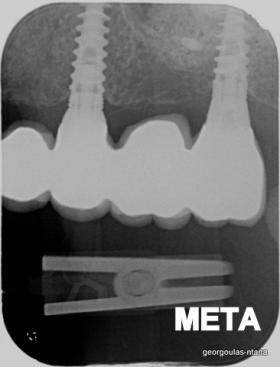

ΟΛΙΚΗ ΑΠΟΚΑΤΑΣΤΑΣΗ ΑΝΩ Κ ΚΑΤΩ ΓΝΑΘΟΥ ΜΕ ΕΜΦΥΤΕΥΜΑΤΑ, ΑΜΕΣΗ ΦΟΡΤΙΣΗ Κ ΑΝΟΙΚΤΗ ΑΝΥΨΩΣΗ ΙΓΜΟΡΕΙΟΥ

Η ασθενής αυτή είχε παλιές ακίνητες αποκαταστάσεις (γέφυρες) στην άνω γνάθο  κ μια κινητή προσθετική αποκατάσταση (μερική οδοντοστοιχία-"μασελάκι") στην κάτω γνάθο. Ήταν δυσαρεστημένη τόσο με την εμφάνιση όσο και με τη λειτουργία των δοντιών της καθώς παραπονιόταν ότι  είχαν εντονη κινητικότητα ενώ και οι προσθετικές τους εργασιές δεν ήταν σταθερές. Η πρόγνωση των δοντιών κρίθηκε φτωχή με αποτέλεσμα να μην είναι δυνατή η συμμετοχή τους σε μια νεα προσθετική αποκατάσταση με μακροχρόνια διάρκεια. Η ασθενής επιθυμούσε οι νέες αποκαταστάσεις να είναι σταθερές και ακίνητες.  Για το λόγο αυτό αποφασίστηκε η ολική αποκατάσταση της άνω κ κάτω γνάθου με ακίνητες επιεμφυτευματικές εργασίες. Στην αριστερή πλευρά της άνω γνάθου, λόγω μη επαρκούς οστού για την τοποθέτηση εμφυτευμάτων προηγήθηκε επέμβαση ανοιχτής  ανύψωσης ιγμορείου άντρου με τη χρήση πιεζοχειρουργικού μηχανήματος ώστε να δημιουργηθεί το κατάλληλο οστικό υπόστρωμα. Ακολούθησε σε επόμενο χειρουργείο η εξαγωγή των υπάρχοντων δοντιών κ η άμεση τοποθέτηση εμφυτεύματων (άμεση εμφύτευση) κ δύο μέρες μετά η τοποθέτηση προσωρινής εργασίας επί των εμφυτευμάτων (άμεση φόρτιση) με αποτέλεσμα η ασθενής να μη μείνει καθόλου χωρίς δόντια κ να είναι καλυμένη αισθητικά όσο καιρό διήρκησε η εργασία